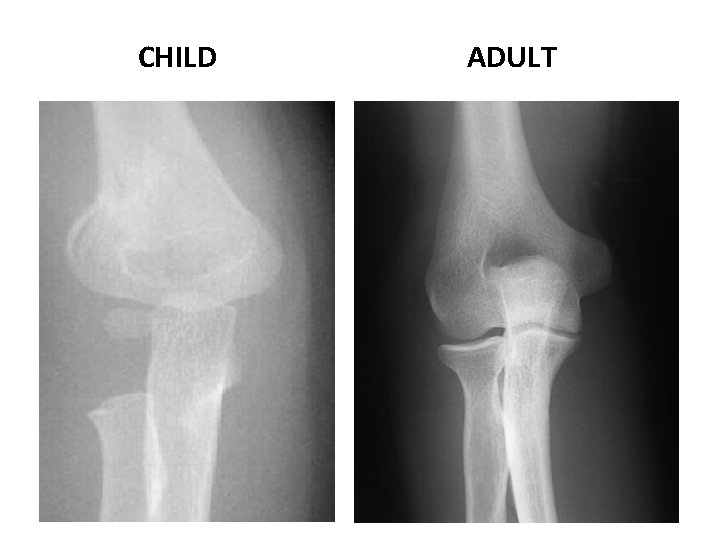

CHILD ADULT